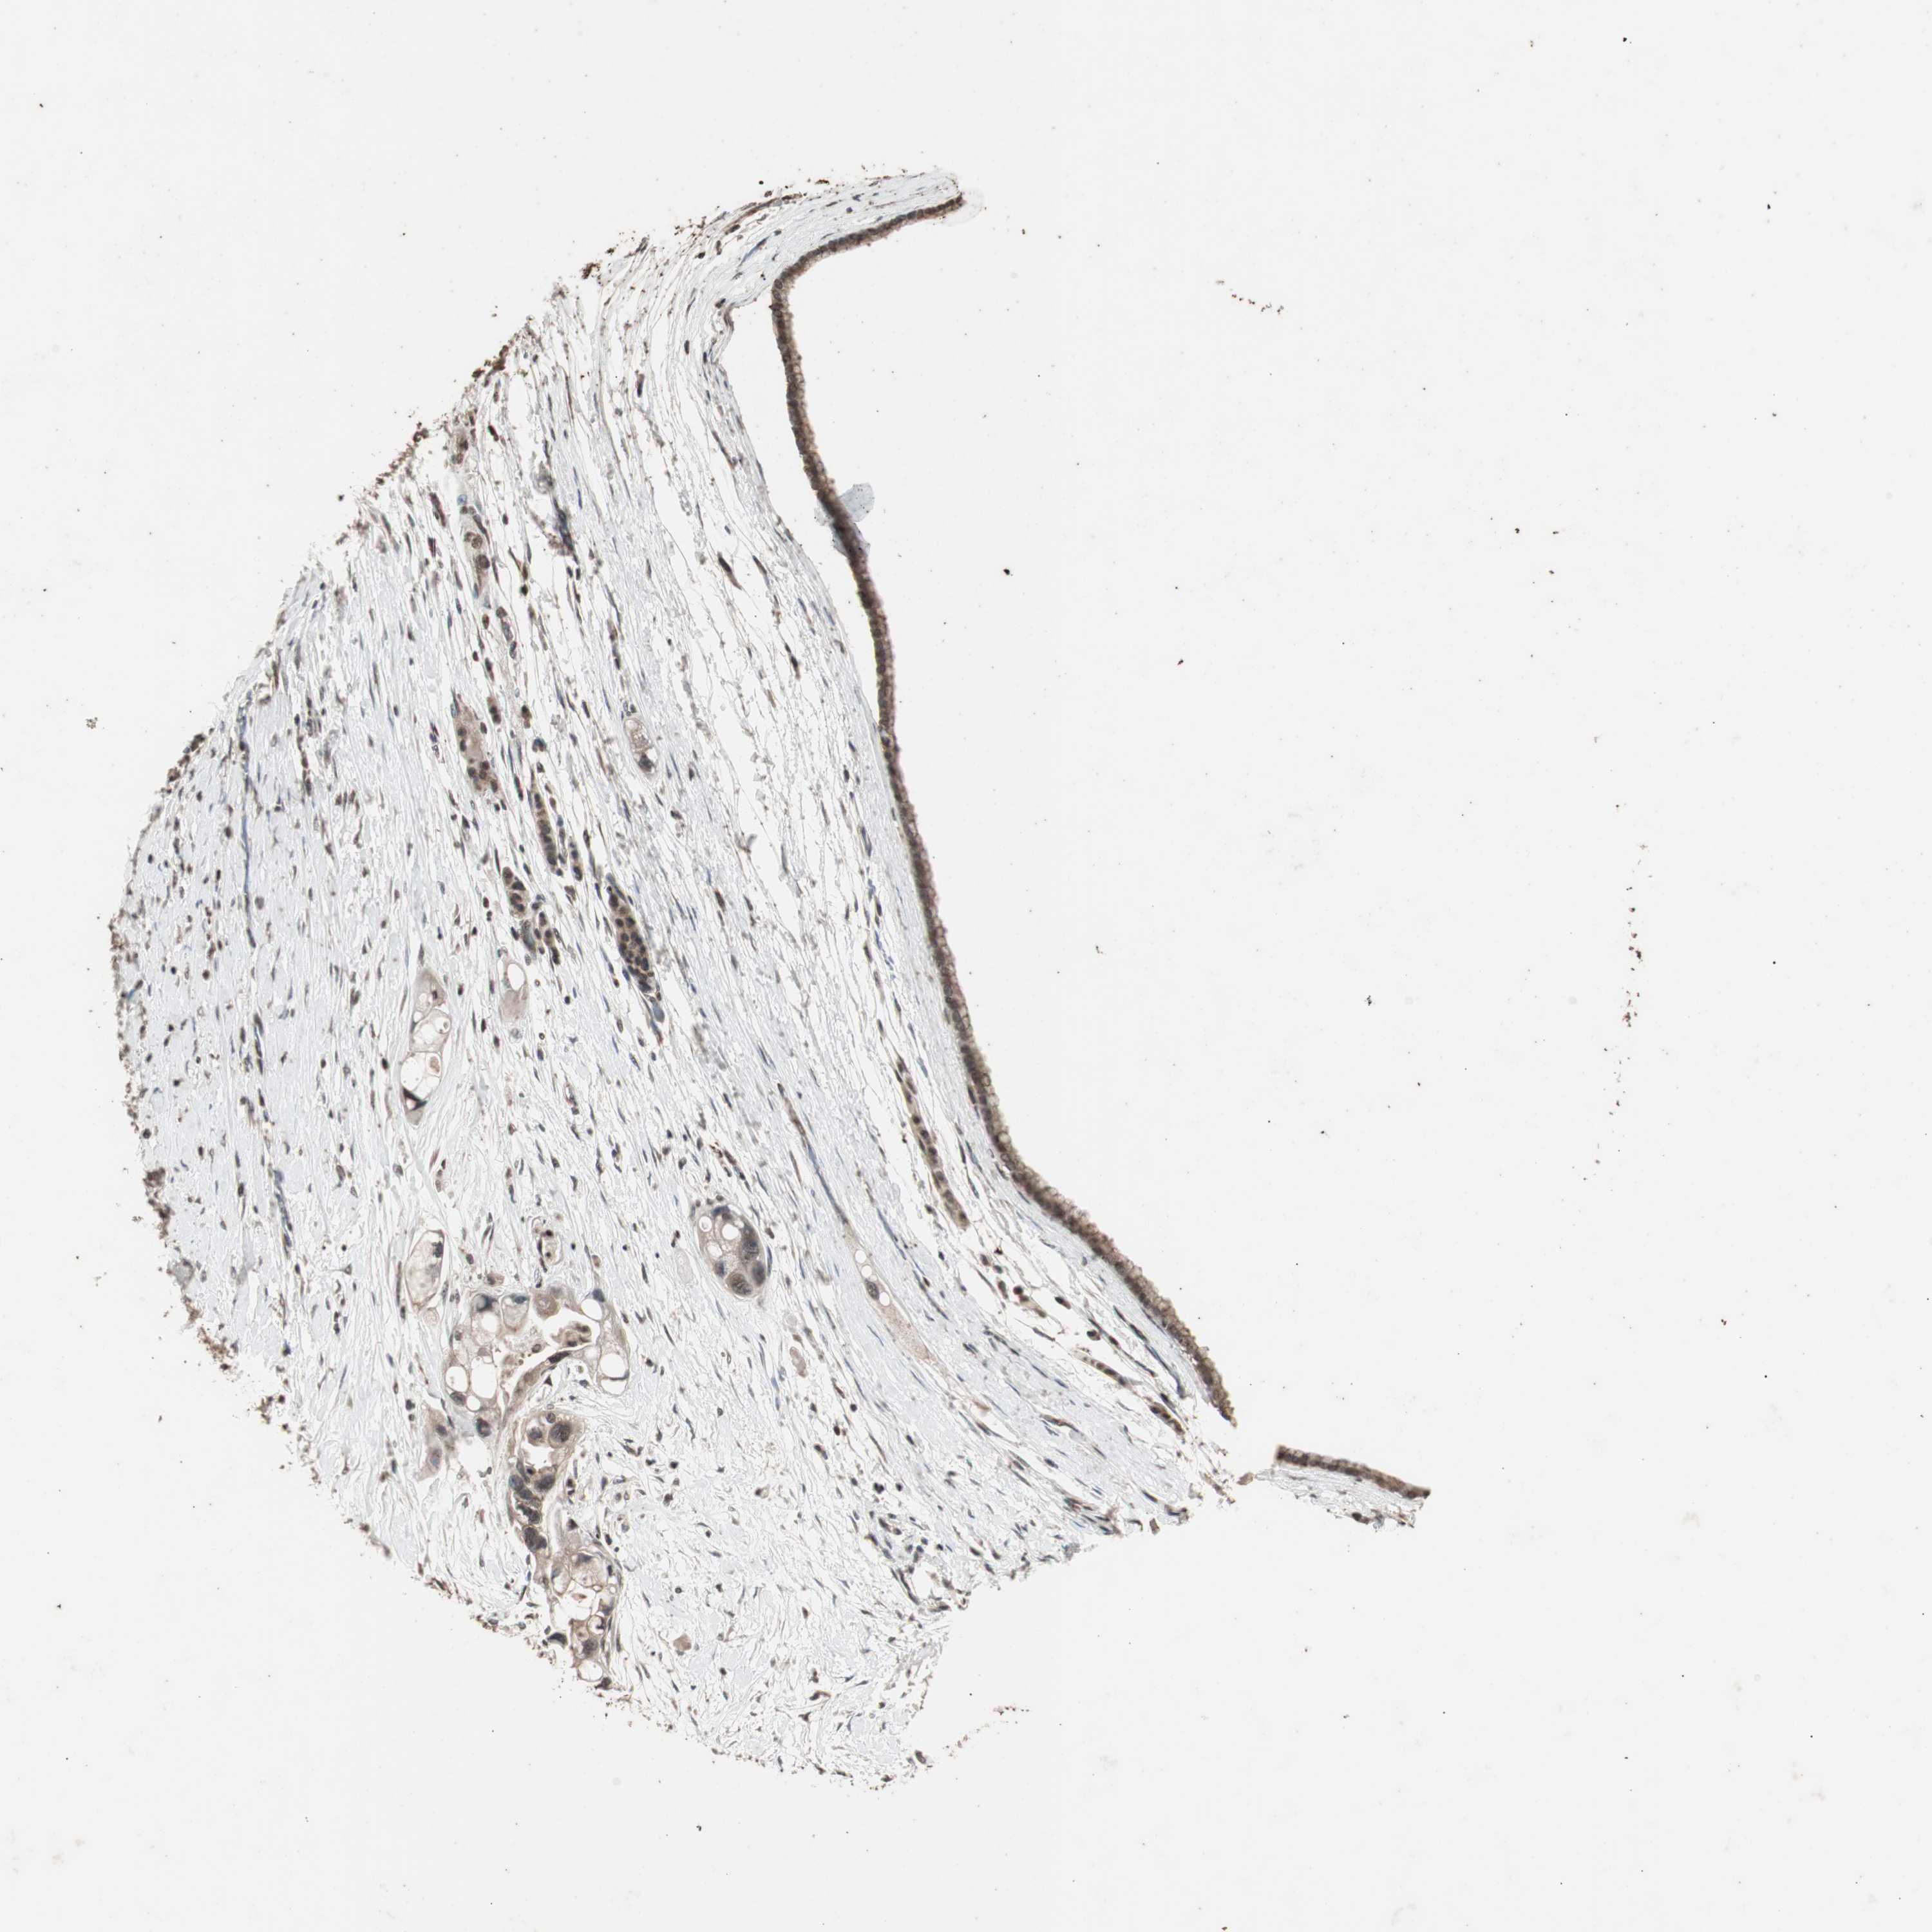

PANCREATIC CANCER - Protein expressioni

A mouse-over function shows sample information and annotation data. Click on an image to view it in a full screen mode. Samples can be filtered based on level of antibody staining by selecting one or several of the following categories: high, medium, low and not detected. The assay and annotation is described here.

Note that samples used for immunohistochemistry by the Human Protein Atlas do not correspond to samples in the TCGA dataset.

Antibody stainingi

Antibody staining in the annotated cell types in the current human tissue is reported as not detected, low, medium, or high, based on conventional immunohistochemistry profiling in selected tissues. This score is based on the combination of the staining intensity and fraction of stained cells.

Each image is clickable and will lead to virtual microscopy that enables deeper exploration of all samples and also displays staining intensity scores, fraction scores and subcellular localization as well as patient and tissue information for each sample.

Antibody HPA007072

Antibody HPA007151

Adenocarcinoma, NOS